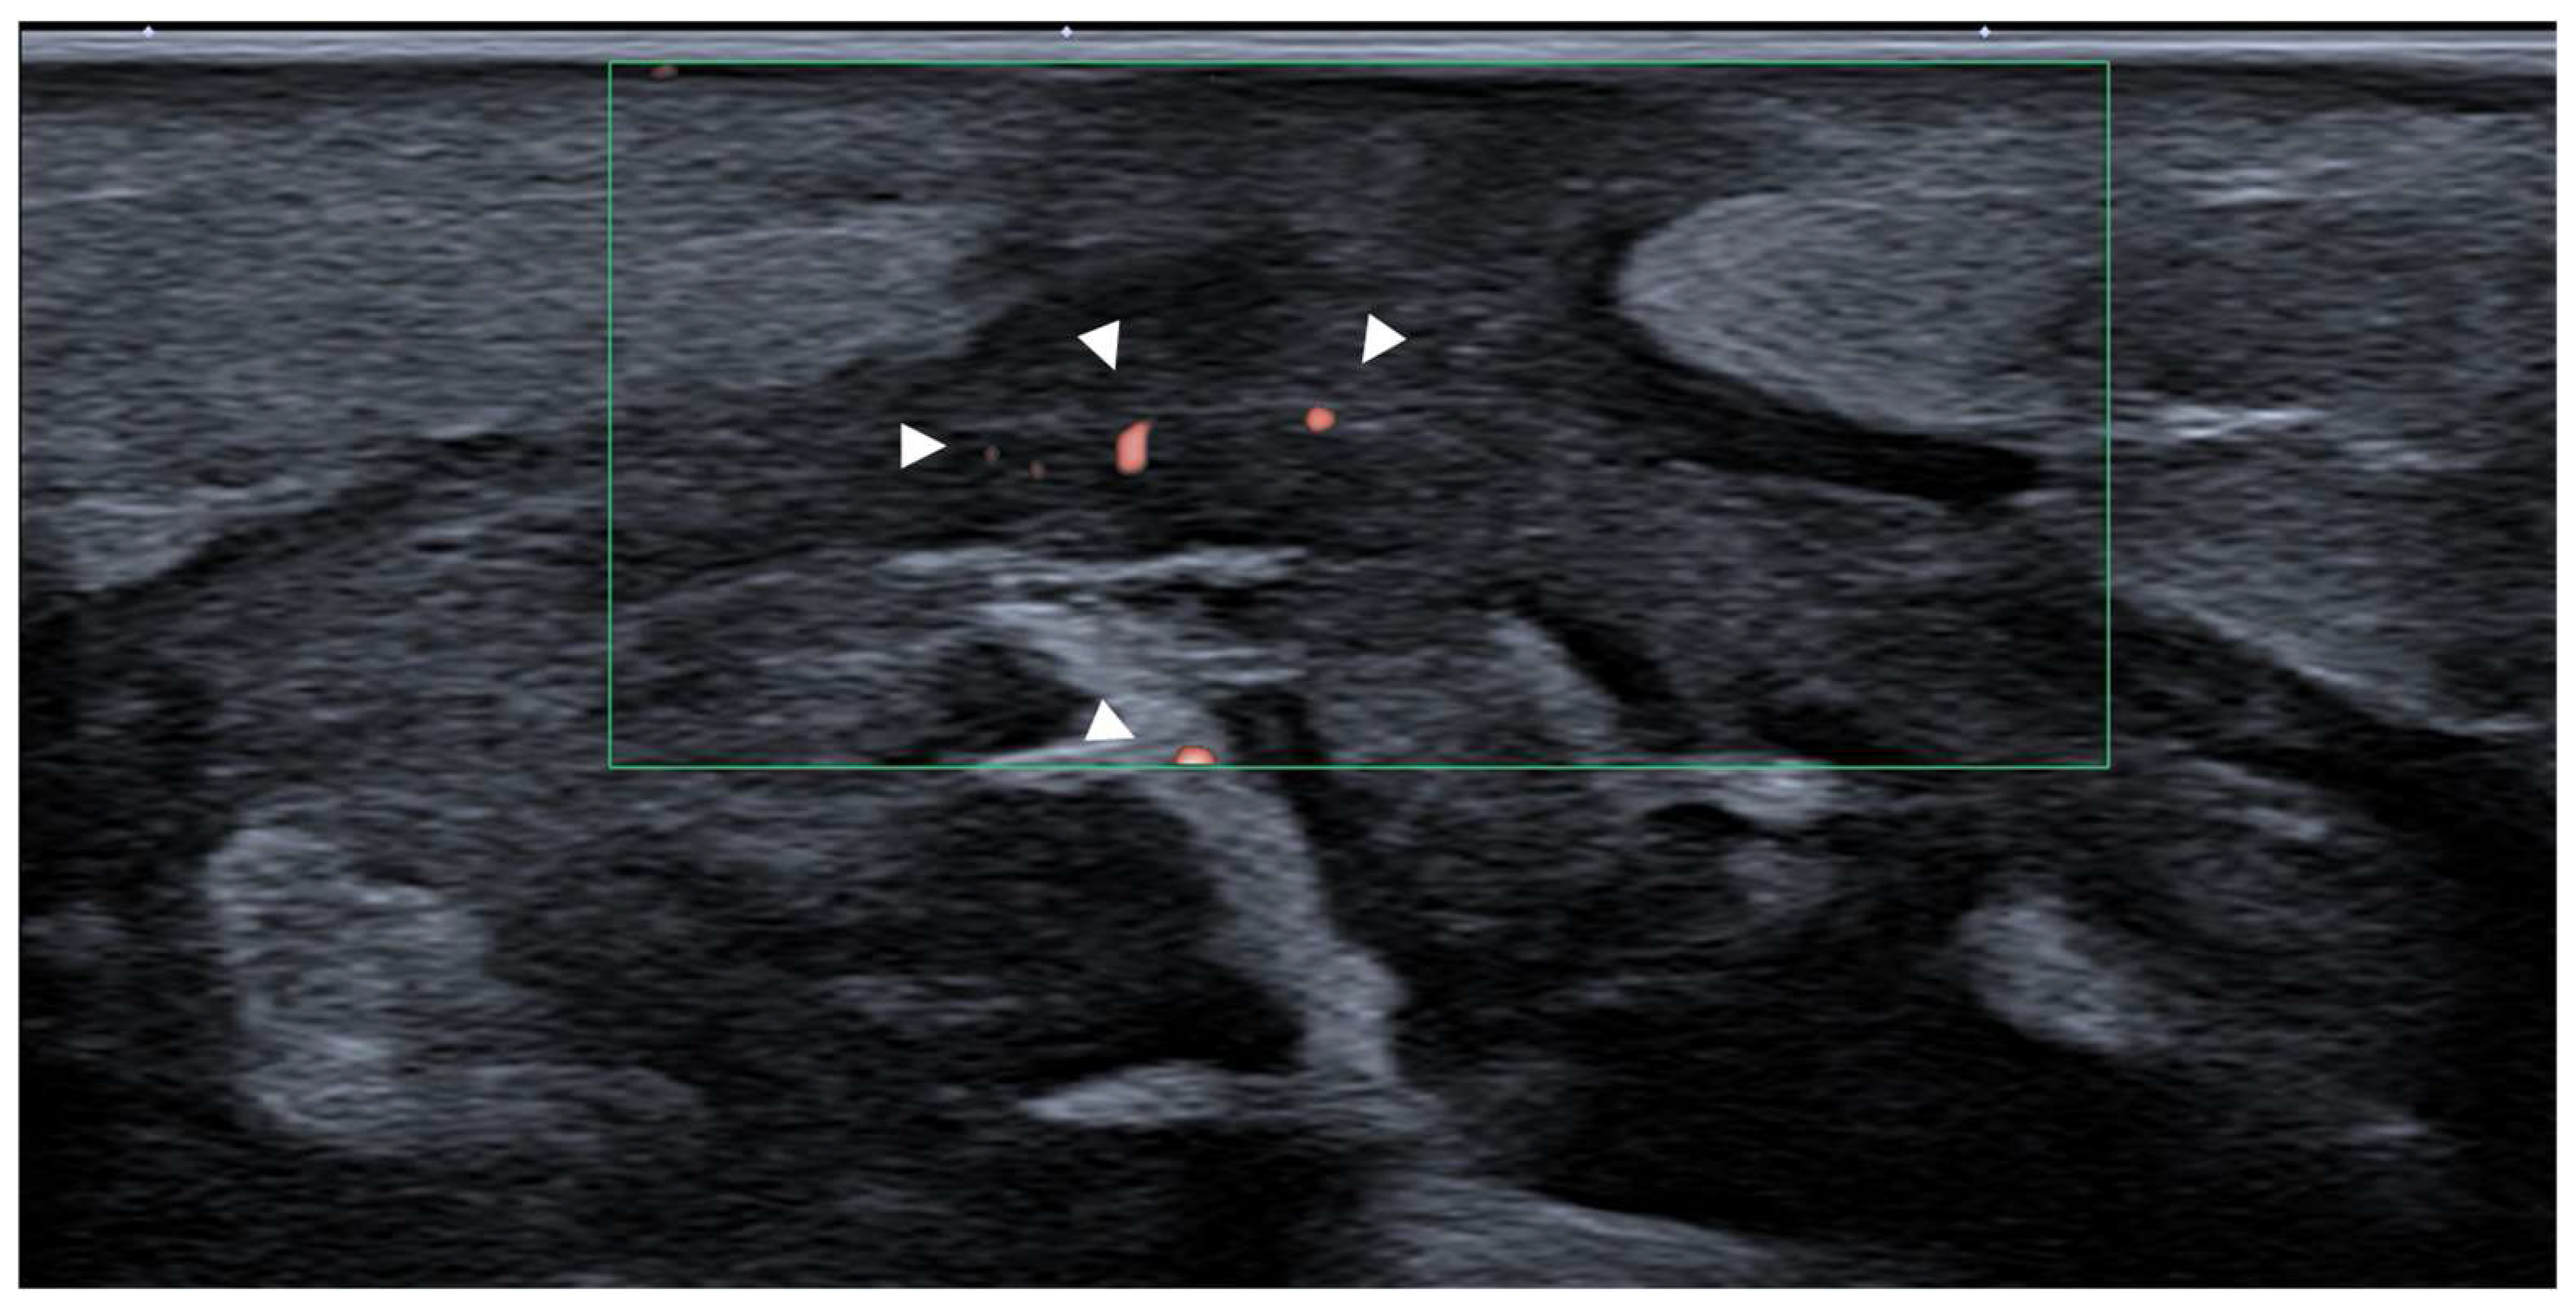

3.5.3. Myofascial Trigger Points